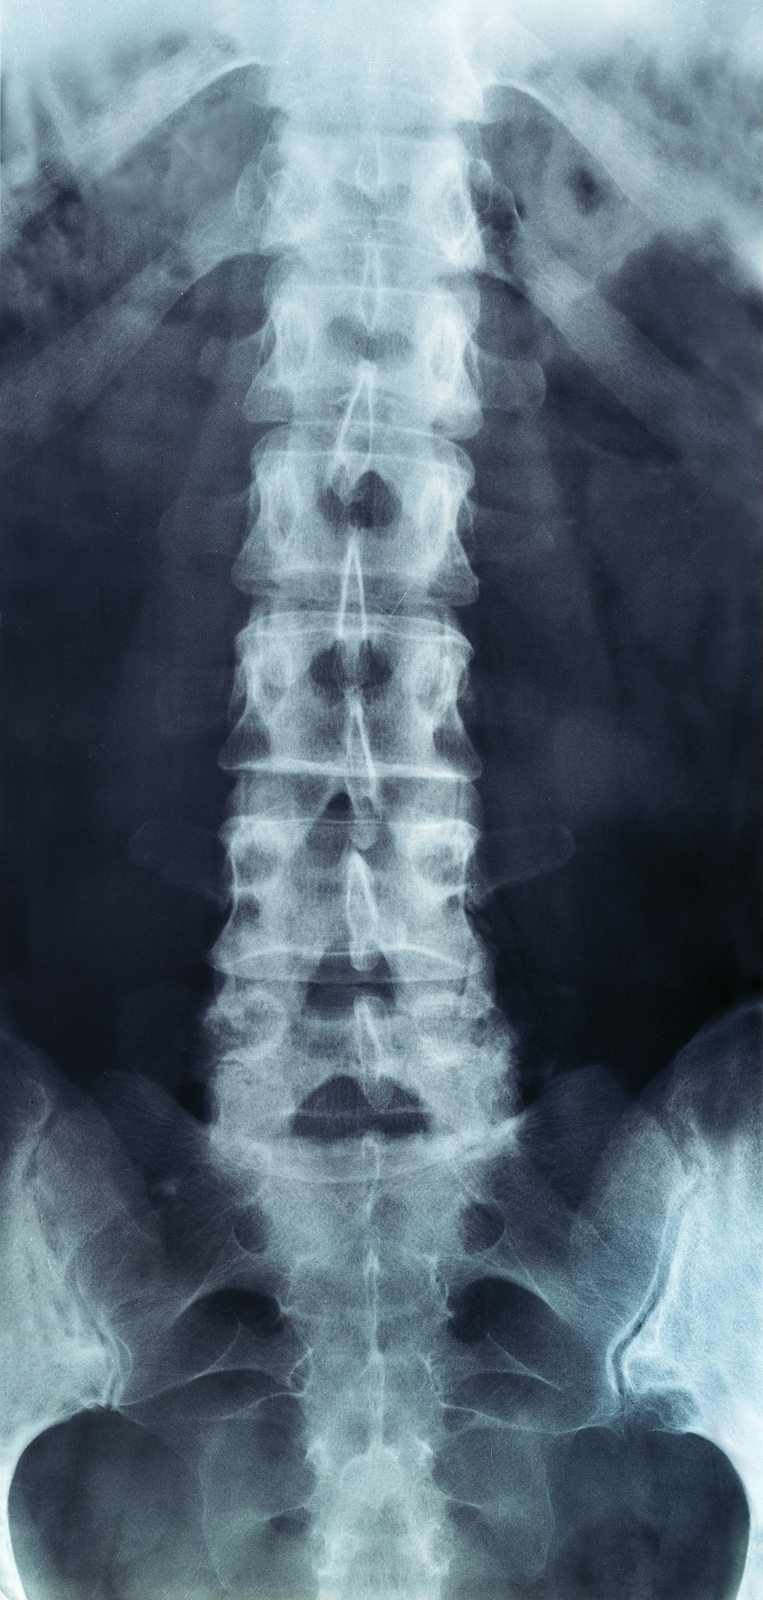

The human spine is made up of 24 spinal bones, called vertebrae, as well as the sacrum and the coccyx. The sacrum is a triangular bone near the bottom of the spine and the coccyx is more commonly known as the tailbone.

Vertebrae are stacked on top of one another to create the spinal column. The spinal column gives the body its form and helps sustain an upright position.

The lumbar spine—where pain is often experienced—is made up of five vertebrae positioned near the bottom of the spinal column. Doctors often refer to these vertebrae as levels L1, L2, L3, L4 and L5. The ‘L’ refers to ‘lumbar’. The lowest vertebra, L5, is connected to the top of the sacrum—a triangular bone at the base of the spine that is located between the two pelvic bones. Some people are born with an extra or sixth lumbar vertebra called L6. Having an extra vertebra doesn't usually cause physical problems.

Most people with low back pain will NOT need x-rays or other tests to diagnose and treat their pain. In some cases, if an x-ray or other diagnostic could be helpful, your physical therapist will refer you to a doctor for further diagnostic imaging.

X-rays are usually the first test ordered before any of the more specialized tests are completed. X-rays use electromagnetic radiation to show problems with bones and can also reveal problems such as fractures, infections, or bone tumors. X-rays of the spine can give your doctor information about bone alignment and can demonstrate how much degeneration has occurred in the spine. Both alignment and degeneration can affect the amount of space in the neural foramina and between the discs, which subsequently impacts the nerves in the area. This is important information your health care professional can use to establish a treatment plan.